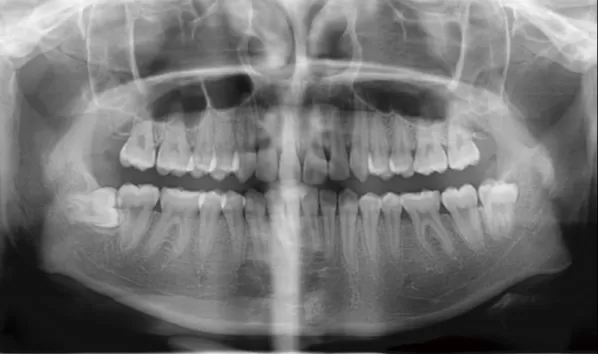

Rayons X avant le traitement

[Radiographie panoramique/Céphalogramme latéral]